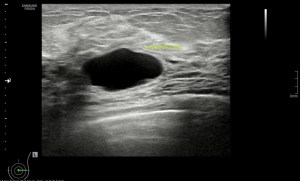

El paciente viene por un bulto en la parte derecha de la espalda, en la región paradorsal alta. Con una sonda de alta frecuencia accedo a la región, que era palpable. Lo primero que observo es que la transmisión del paciente no es buena, esto que a veces pasa que encuentras pacientes, que no sé explicar el motivo, no transmiten bien.

Me da para observar que en la zona de palpación encuentro, profundo en la imagen, un formación hiperecogénica, que está dentro de un músculo. Antes de detallar los hallazgos de la imagen lo que quise fue reconocer bien la anatomía. La piel y el tejido celular subcutánea era muy fácil, también saber que esta anatomía superficial estaba intacta y que la lesión estaba intramuscular, pero me encontraba dos planos musculares, uno superficial, el otro profundo, el profundo con la lesión.

Me tuve que ir al atlas de anatomía para saber cuál era el músculo que estaba debajo del músculo trapecio, que tenía claro que era el superficial. Bien, el músculo que ocupaba el segundo plano en profundidad era el músculo Romboides, que te enlazo para que sepas más de su posición y función.

El protocolo es el típico, cortes en eje corto y largo, con doppler, para comprobar vascularización, como línea roja del lipoma. Imágenes 3,4 y 6.

Después con la radióloga, hicimos una imágenes con «panoramic view» que te dan un detalle de las anatomía con respecto del lado contralateral, sano. Imagen 1.

La lesión era ovalada, hiperecogénica, ocupaba gran parte del músculo, pero respetaba parte de este, que era hipoecogénico (imagen 5), recuerda que así es por definición y que ésta ecogenicidad del músculo es referencia para el resto de ecogenicidades del aparato locomotor. Como te he contado, no había doppler color ni en modo angio.